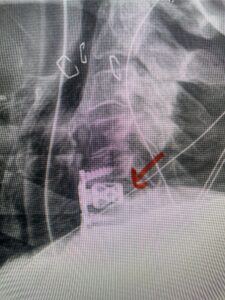

The case illustrates a more subtle finding of cervical myelopathy in a young 52 year-old male who presents with 5 months of left upper extremity weakness and burning. He also had developed over the last two months pain in his right upper extremity. He also had difficulty with fine motor skills. He had a positive Hoffman reflex and mild 4-4+ long tract weakness of his left arm and leg. Cervical MRI revealed an explanation for the patient’s symptoms (Fig. 7) as it revealed a disc osteophyte complex causing some cord flattening, slightly more to the left. We performed a C5-6 anterior cervical discectomy and interbody fusion with cage and plate (Fig. 8) He had a significant improvement in his weakness, numbness, and pain. What is interesting is that this was a relatively young patient without severe cord compression but was significantly affected by a mild amount of cord compression. This may speak to how a younger spinal cord may react much more adversely perhaps secondary to a less compliant spinal cord.

Fig 8: lateral intraoperative cervical x-ray demonstrating placement of interbody cage and plate at C5 6 (red arrow)